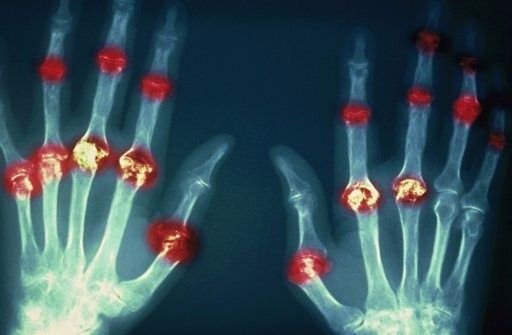

?類風(fēng)濕關(guān)節(jié)炎

類風(fēng)濕關(guān)節(jié)炎是一種高度致殘的自身免疫性疾病,發(fā)病十年的患者中至少有50%的人失去勞動能力。

類風(fēng)濕關(guān)節(jié)炎©Health Same of Flickr

1977年,Baldwin在用骨髓干細(xì)胞移植治療再生障礙性貧血的過程中,意外發(fā)現(xiàn)患者的類風(fēng)濕關(guān)節(jié)炎得到緩解。

2004年,歐洲骨髓移植和抗風(fēng)濕病聯(lián)盟對60例類風(fēng)濕病關(guān)節(jié)炎移植患者進(jìn)行回顧性分析,這些患者的關(guān)節(jié)破壞都達(dá)到不可修復(fù)程度,生活不能自理,通過干細(xì)胞移植治療后,67%的患者得到明顯緩解。

我國國內(nèi)多家醫(yī)院已開展了干細(xì)胞治療類風(fēng)濕性關(guān)節(jié)炎的臨床研究。首例自體干細(xì)胞移植治療類風(fēng)濕關(guān)節(jié)炎在北京協(xié)和醫(yī)院完成。經(jīng)過5個月隨訪,這些經(jīng)常規(guī)藥物治療失敗且病情發(fā)展迅速的患者,在接受干細(xì)胞移植治療后,癥狀均獲得改善,關(guān)節(jié)腫脹消失,各項檢查指標(biāo)恢復(fù)正常。

解放軍323醫(yī)院2011年的一項臨床研究中,27位患者(對照組)只使用藥物治療;另外153位患者(細(xì)胞治療組)在藥物治療的基礎(chǔ)上進(jìn)行臍帶間充質(zhì)干細(xì)胞輸注。結(jié)果顯示,治療組DAS28、HAQ 評分、ACR20較對照組下降明顯(分值越低,療效越好),Th1/Th2趨于平衡、Treg升高與臨床實驗指標(biāo)及癥狀的緩解直接相關(guān)。